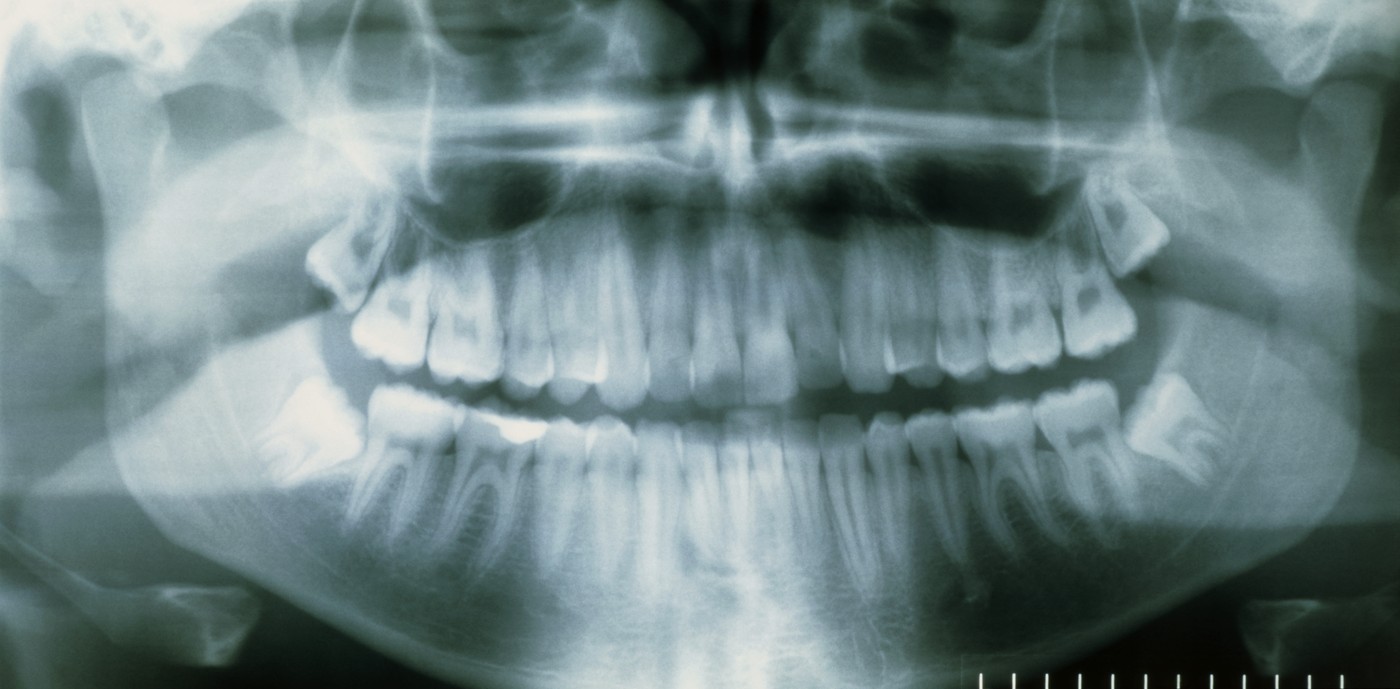

Vozlič priporoča, da vsakdo takrat, ko modrostni zobje običajno začnejo izraščati – torej pri okoli 17. ali 18. letu – obišče svojega zobozdravnika. Ta bo opravil rentgensko diagnostiko (sliko, imenovano ortopan) in tako ocenil, ali bi bilo osmice dobro odstraniti. Če je zob pravilno izraščen in ga lahko enostavno izpuli sam, lahko to stori sam. Če je potrebna kirurška odstranitev, zobozdravniki paciente napotijo k maksilofacialnemu ali oralnemu kirurgu.

Na prvem pregledu bo ta najprej še enkrat ocenil, ali je odstranitev smiselna in po potrebi naroči še dodatno slikovno diagnostiko, kot je na primer 3D-slikanje, imenovano CBCT. Dodatno slikanje je lahko potrebno, če se ob zobu dogaja kakšna sumljiva sprememba ali pa je modrostni zob v bližini živca.